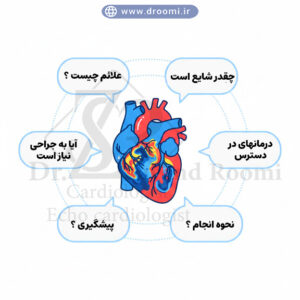

علائم و نشانههای بیماری دریچه قلب که نیاز به اکو داپلر رنگی دارند

بسیاری از بیماریهای دریچه قلب در مراحل اولیه بدون علامت هستند، اما با پیشرفت، علائم مشخصی ظاهر میشوند که هشداردهندهاند. تشخیص زودهنگام با اکوکاردیوگرافی داپلر دریچه قلب میتواند از عوارض جدی مانند نارسایی قلبی جلوگیری کند. اگر هر یک از این علائم را تجربه میکنید، مراجعه به متخصص برای انجام اکو رنگی قلب برای دریچه میترال یا دیگر دریچهها ضروری است.

تنگی نفس، خستگی، تپش قلب و درد قفسه سینه

تنگی نفس، به ویژه هنگام فعالیت یا دراز کشیدن، یکی از شایعترین علائم نارسایی دریچه قلب است که ناشی از تجمع مایع در ریهها میباشد. خستگی مزمن و کاهش تحمل فعالیت نیز رایج است، زیرا قلب برای جبران مشکل دریچهای بیشتر کار میکند. تپش قلب (پالپیتاسیون) و درد قفسه سینه، شبیه به آنژین، میتواند در تنگی آئورت یا نارسایی شدید ظاهر شود. این علائم اغلب نیاز به ارزیابی فوری با اکو داپلر رنگی برای تنگی آئورت دارند تا شدت مشکل مشخص گردد.

سوفل قلبی و ادم

سوفل قلبی، صدایی غیرعادی که پزشک با گوشی پزشکی میشنود، نشانه کلاسیک مشکلات دریچهای است و اغلب اولین سرنخ برای درخواست اکوکاردیوگرافی میباشد. ادم (تورم) در پاها، مچ پا یا شکم نیز به دلیل احتباس مایع ناشی از نارسایی قلب رخ میدهد. در شیراز، بهترین متخصص اکوکاردیوگرافی دریچه قلب در کلینیک دکتر سوندرومی میتواند با استفاده از اکو داپلر رنگی این علائم را به مشکلات دقیق دریچهای مرتبط کند و برنامه درمانی مناسبی ارائه دهد.

تشخیص بهموقع این علائم با روشهای پیشرفته نه تنها درمان را آسانتر میکند، بلکه کیفیت زندگی را حفظ مینماید. اگر علائم مشابهی دارید، هرچه زودتر اقدام کنید.